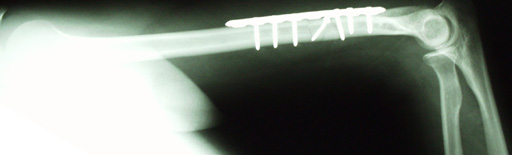

Upon my arrival at Boulder Community Hospital, some X-rays were taken...

Something’s a bit amiss here…

Boy, I tell you what, that bone ain’t right.

Ummm…OUCH!!